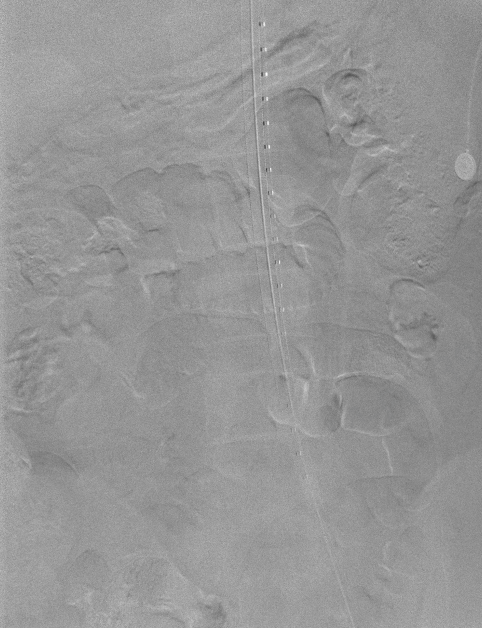

手术过程

1、穿刺患者左侧颈动脉与右股动脉,并在左颈动脉置入7F的穿刺鞘后,导入软导丝,自上而下地探索真腔,在穿出右股动脉后,从左股动脉导入9F长鞘至降主动脉,先后在长鞘内交换导丝为超硬导丝,分支导丝和造影导管导丝,下撤长鞘后,上推黄金标记导管至升主动脉造影;

动脉长鞘怎么置入【弓部重建直通车】真腔难觅,另辟蹊径|潍坊市人民医院血管外科运用Castor®支架结合长鞘建立导丝通路治疗主动脉夹层两例_https://www.jmylbn.com_新闻资讯_第15张

术前造影